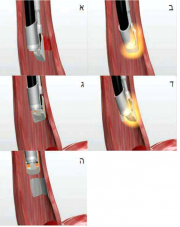

| 09:41, 18 ביוני 2013 | איטומי חריצים7.png (קובץ) |  |

66 קילו־בייטים | Motyk | 1 | |

| 09:33, 18 ביוני 2013 | איטומי חריצים6.png (קובץ) |  |

47 קילו־בייטים | Motyk | 1 | |

| 09:10, 18 ביוני 2013 | איטומי חריצים5.png (קובץ) |  |

77 קילו־בייטים | Motyk | 1 | |

| 09:07, 18 ביוני 2013 | איטומי חריצים4א.png (קובץ) |  |

159 קילו־בייטים | Motyk | 1 | |

| 09:04, 18 ביוני 2013 | איטומי חריצים4.png (קובץ) |  |

111 קילו־בייטים | Motyk | 1 | |

| 08:57, 18 ביוני 2013 | איטומי חריצים3.png (קובץ) |  |

124 קילו־בייטים | Motyk | 1 | |

| 08:55, 18 ביוני 2013 | איטומי חריצים2.png (קובץ) |  |

105 קילו־בייטים | Motyk | 1 | |

| 08:48, 18 ביוני 2013 | איטומי חריצים1.png (קובץ) |  |

194 קילו־בייטים | Motyk | 1 | |